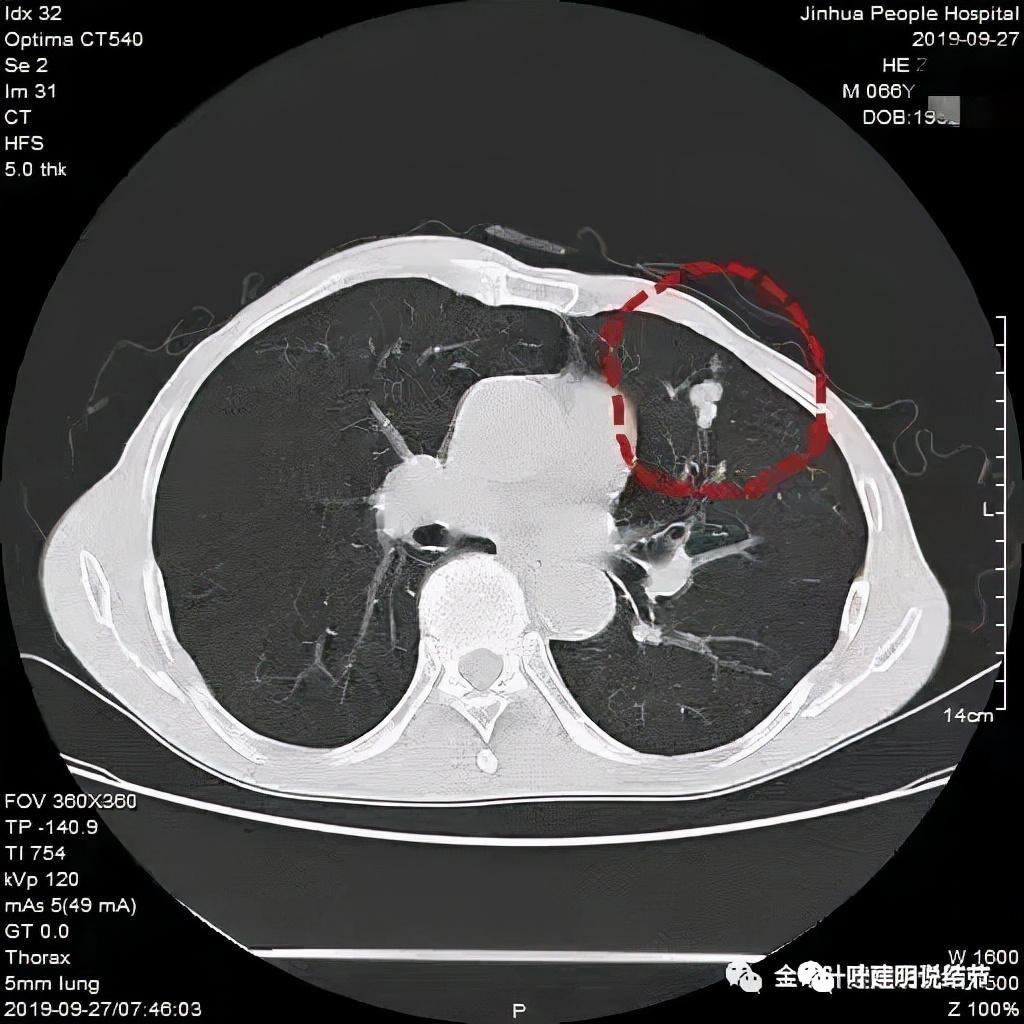

临床上我们容易见到小细胞原发灶不大,但广泛的纵隔淋巴结转移,甚至远处转移的,而且中央型多见,这时候,诊断不难。但若病灶是周围型,淋巴结肿大又不明显或不广泛,而原发灶又像这样边缘光滑的,还真倒容易误诊。之前碰到过一例小细胞肺癌是下面这样的:

左上叶簇状实性小结节,呈堆积状。开始时也没有能考虑到肺癌,是因为随访后病灶增大,经过穿刺活检确诊为小细胞肺癌。其实今天这个病例也是堆积的,也是两处病灶,只是挨的近而已。所以以后如果碰到“实性结节堆积状”的,边缘光滑缺乏收缩力或膨胀性的、周围又没有炎性渗出改变的,我们要考虑到其小细胞肺癌的可能性,而且可能性不小!